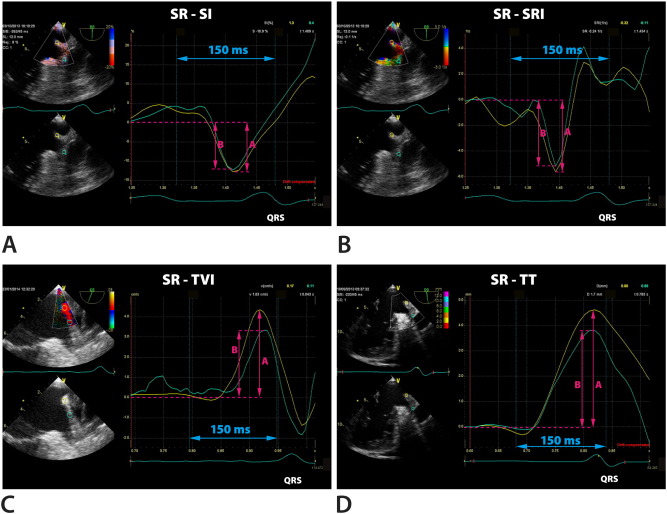

Fig. 5

Fig. 5.

Q-analysis in patient with atrial fibrillation (AF). A sample of measurements (arrows) in the area of left lateral ridge in region A (yellow curves) and in region B (green curves). Panel A: strain imaging (SI). Panel B: strain rate imaging (SRI). Panel C: tissue velocity imaging (TVI). Panel D: tissue tracking (TT).

Off-line analysis was performed with the Q-Analysis software (General Electric EchoPac workstation, version 112; upgrade BT12). The TDI recording at 150 ms before the QRS complex was selected for analysis of the systolic phase in all segments. In TEE in the view enabling visualization of the LAA in the longitudinal axis the TDI sector width was selected that included LLR or BMAS. In patients in SR a fragment of the wave at least at 800–900 ms between the QRS complexes before was chosen for analysis. In patients with AF, due to the lack of P wave the TDI sector width was selected in the same period between QRS complexes. Then we analyzed average tissue velocity imaging (TVI), strain imaging (SI), strain rate imaging (SRI) and deformation (tissue tracking, TT) in each area A, B and C in all patients. Atrial systolic parameters could be measured in the late diastolic phase of the mechanical ventricular cycle. Therefore such systolic strain reflecting the extent of myocardial fiber shortening was evaluated as the lowest value below the baseline. For correct presentation the tracking start was placed at the top of the P wave, whereas the tracking end immediately after the QRS complex. Similarly, in SRI we analyzed the lowest value at 150 ms before the QRS complex. The last parameter to measure was deformation TT, showing the highest deflection of the curve at the same time interval. Then we compared peak values obtained in PW-TDI as well as TVI, SI, SRI and TT measured at A, B and C in groups with SR and AF. In patients with AF those with and without LAA thrombus were analyzed separately. Fig. 4 ;  Fig. 5 show an example of measurements at A, B and C in patients in SR and AF, respectively. Differences in TVI, SI, SRI and TT between A, B and C in patients in SR and AF were then submitted for statistical analysis. Additional analyses of subgroups with and without thrombus in LAA were also made.